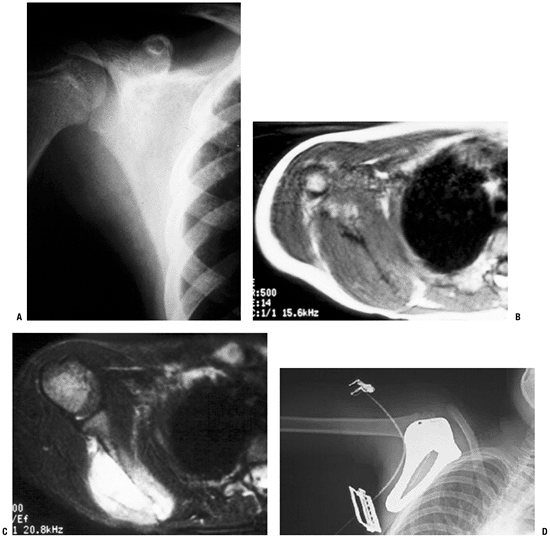

This specific expandable prosthesis has a deformable resin, which, when

spring device. The expansion procedure does not require a skin incision.P.71![]() Figure 4.3-12 This patient with Ewing sarcoma of the right scapula shown on plain radiograph (A) and T1-weighted (B) and T2-weighted (C) axial magnetic resonance images underwent scapulectomy and prosthetic scapular reconstruction (D), maintaining the integrity of the proximal humeral metaphysis following neoadjuvant chemotherapy.P.72 Figure 4.3-12 This patient with Ewing sarcoma of the right scapula shown on plain radiograph (A) and T1-weighted (B) and T2-weighted (C) axial magnetic resonance images underwent scapulectomy and prosthetic scapular reconstruction (D), maintaining the integrity of the proximal humeral metaphysis following neoadjuvant chemotherapy.P.72 Figure 4.3-13 A proximal humeral osteosarcoma (A) has been reconstructed using an allograft–prosthetic composite reconstruction (B,C). Figure 4.3-13 A proximal humeral osteosarcoma (A) has been reconstructed using an allograft–prosthetic composite reconstruction (B,C).

The intraoperative photo shows dual 90:90 plate fixation of the

allograft and sutures being used to repair the host rotator cuff to the

allograft rotator cuff (C).P.73![]() Figure 4.3-14 This patient with metastatic renal carcinoma to the right proximal humerus (A) Figure 4.3-14 This patient with metastatic renal carcinoma to the right proximal humerus (A)

underwent resection and reconstruction using a proximal humeral

replacement endoprosthesis, shown here intraoperatively prior to

reduction and closure (B).